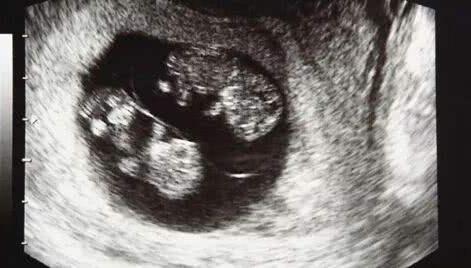

一段时间过后,在俩人身体状态差不多的时候又开始进入了备孕阶段,这一次两个人都很小心,第8周的时候去了医院做产检,这次的检查结果给小夫妻俩带来了惊喜,不仅怀孕,还是"双胞胎",一回家就迫不及待的把这个消息告诉了家人,开心的合不拢嘴。

但不幸的是又一次,到她怀孕第32周的时候,家人陪她来医院做检查,晴天霹雳一样的事情发生再次击垮了她,"又一次胎停了",这已经是她经历过的第三次胎停。况且这次怀的还是双胞胎,几乎接近崩溃边缘的她不敢相信,又做了一次彩超,但结果都是一样,确实是胎停了。家里人知道后伤心欲绝:"上辈子造了什么孽啊、真的要断子绝孙吗?"她听到更是难过了......